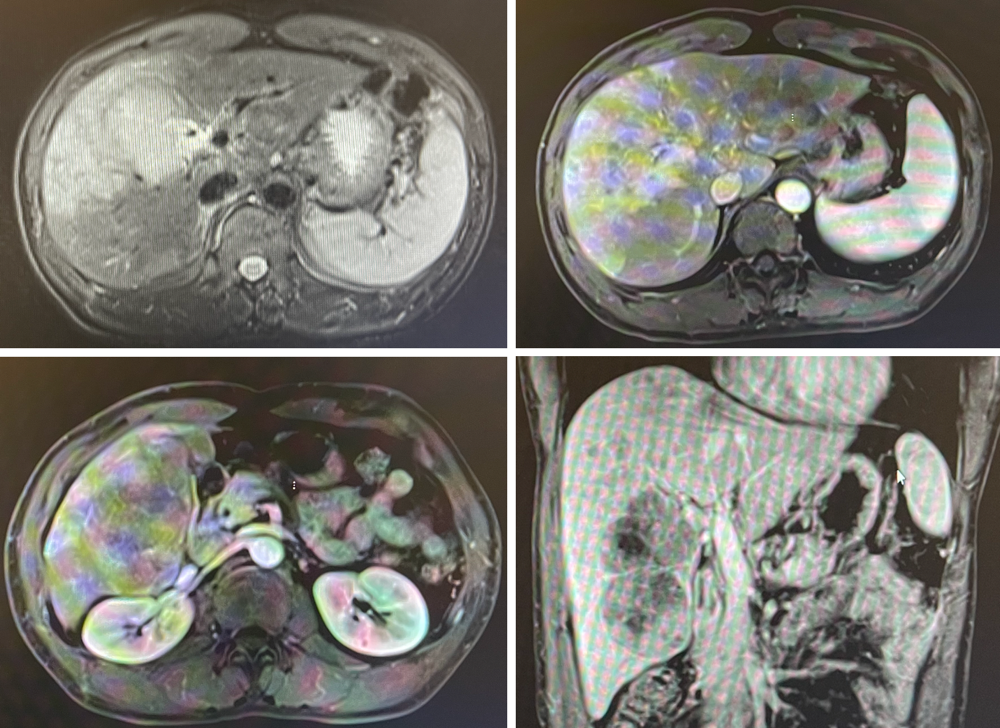

病史概要

● 男性,40岁;

● 主诉:发现肝占位5日

● 病史:5日前无明显诱因出现肝区痛,当地医院腹部增强CT:肝MT合并肝内转移,门静脉癌栓

● 肿瘤标志物:AFP(>60500ng/mL)

● 诊断:肝细胞肝癌

影像学检查

桡动脉鞘怎么读R.A.V.I.Club微课堂 · 经桡动脉外周介入之复旦中山篇第十一期_https://www.jmylbn.com_新闻资讯_第20张